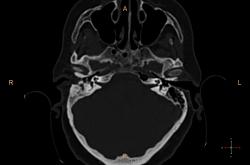

Справа в полости среднего уха небольшое количество жидкости? Пирамида и сосцевидный отросток склерозированы. У нас направляют на КТ только при подозрении на деструкцию или опухоль. Исследование выполняются на специальной программе для височных костей , срезы по 0.1 или 0.05 см, костная структура видна изумительно. А чаще изменения височных костей обнаруживаются как случайная находка при КТ черепа (хорошо видно на "сердечном" режиме).

У нас минимальный срез идет по 0,75мм, мне кажется если есть возможность провести КТ-исследование, следует это делать, что косается данной пациентки, все не так просто, у неё имеется клинически свищ с отделяемым, позади ушной раковины, где имеено и откуда идет свищ четко видно, а так все верно имеется эпитимпанит и антрит.

Согласен, ///если есть возможность провести КТ-исследование, следует это делать///, с Шуллерами-Майерами не сравнить. Кстати, состояние аттико-антральной области обычно более демонстративно на аксиальных срезах уровня латерального полукружного канала.

Касаюсь Андрей Юрьевич, лобарант меня позвал в плане выбора протокола исследования, а я при наложении плоскости сканирование на топограмме, взял и не учел оптико-меатальную линию, получилось несколько неуклюже, поэтому только на станции подорвался выравнивать её при анализе сканов :-(

Свищевой ход.